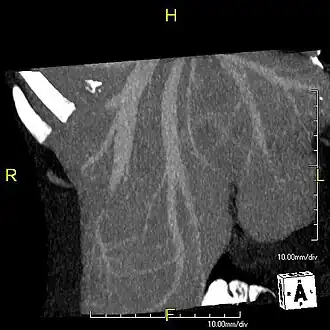

With the recent advances of noninvasive imaging, living liver donors usually have to undergo imaging examinations for liver anatomy to decide if the anatomy is feasible for donation. The evaluation is usually performed by multidetector row computed tomography (MDCT) and magnetic resonance imaging (MRI). MDCT is good in vascular anatomy and volumetry. MRI is used for biliary tree anatomy. Donors with very unusual vascular anatomy, which makes them unsuitable for donation, could be screened out to avoid unnecessary operations.

-

MDCT image. Arterial anatomy contraindicated for liver donation -

MDCT image. Portal venous anatomy contraindicated for liver donation -

MDCT image. 3D image created by MDCT can clearly visualize the liver, measure the liver volume, and plan the dissection plane to facilitate the liver transplantation procedure. -

Phase contrast CT image. Contrast is perfusing the right liver but not the left due to a left portal vein thrombus.